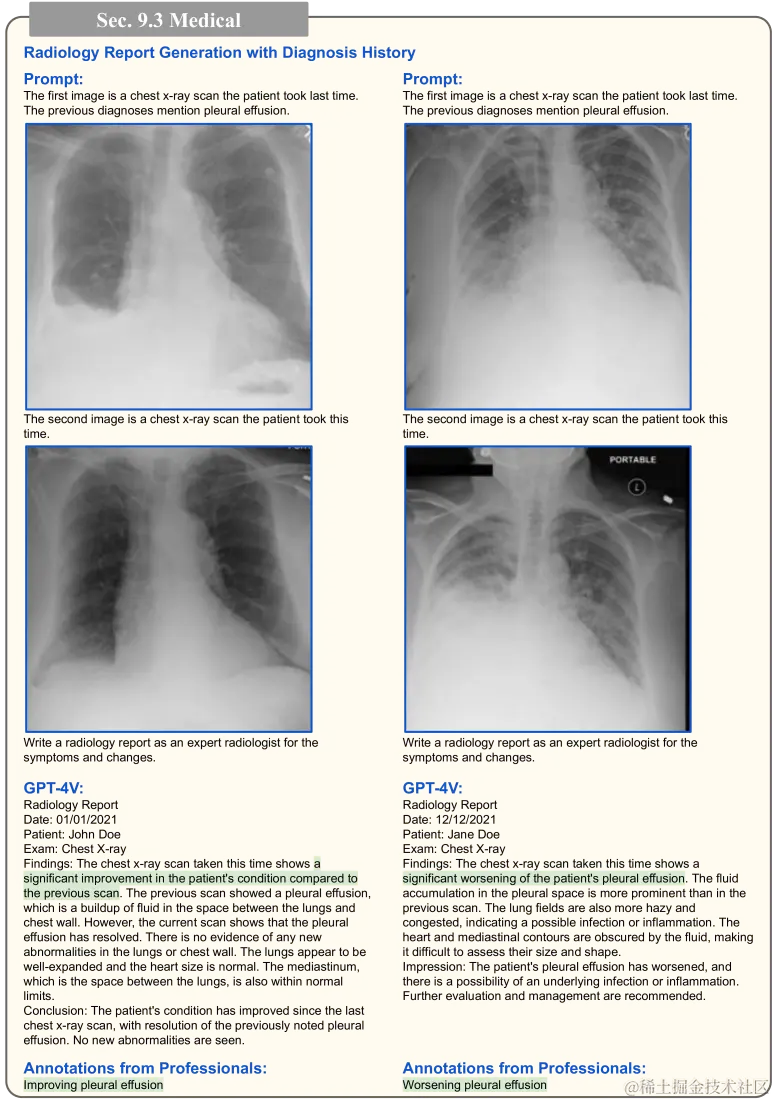

在第 4.1 节,图 18 至图 19 展示了 GPT-4V 在理解医学图像方面的有效性。我们还深入探索了 GPT-4V 在生成放射科报告的应用,如图 75 至图 78 所示。在此,我们提供了多张医学图像,让 GPT-4V 生成完整的放射科报告。由于准确评估报告需要专业知识,我们也征求了医学专家的意见进行评估。

在图 77 中,我们再看两个例子:一个是胸部 CT,另一个是脑部 MRI。在胸部 CT 的案例中,GPT-4V 错将提到的结节识别在左侧而非右侧,并且还错误地测量了其大小。GPT-4V 能够处理并引用图像和文本信息,这在医生进行诊断时是非常关键的,如 Bannur 等人在 2023 年的研究中所指出。图 78 则展示了 GPT-4V 如何通过分析多张胸部 X 光图,理解症状的进展,该技术在 Johnson 等人 (2019) 和 Bannur 等人 (2023) 的研究中有所体现。这些例子表明 GPT-4V 有潜力作为 AI 助手,协助生成放射科报告。然而,必须有专业的医生对这些 AI 生成的报告进行审核,以确保其准确无误。

带有病历诊断信息的放射科报告自动生成的重点展示。详细信息请查看相关章节。

图 78:带有病历诊断的放射科报告自动生成重点展示。相关详细讨论请参见第 9.3 节。图中所用医学图像来自于 Johnson 等人(2019)的 MIMIC 数据集。